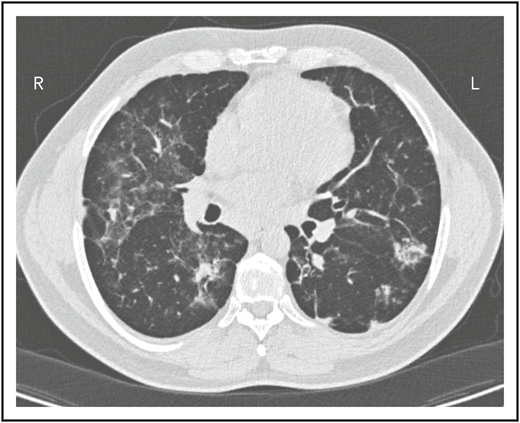

A second common reason for a patient to come to the attention of hematologists is the finding of an enlarged spleen, especially in an adult with lymphadenopathy. This was the reason in patient 2, who is now a 46-year-old male professional dog walker. At the age of 31, he was found to have an enlarged spleen together with cervical and axillary lymphadenopathy. Hematology was consulted, and the lymph node was biopsied; pathology revealed that he had noncaseating granuloma. He was then referred to pulmonology and, with this evidence, was diagnosed with sarcoidosis and treated with steroids for some months, but he stopped the treatment. Although he had no obvious respiratory symptoms over the following 15 years, he had a slow decline in lung function, and chest computed tomography showed hilar lymphadenopathy, ground-glass opacities with nodules, and bronchiectatic changes (Figure 2). In 2018, he had acute bacterial pneumonia, became concerned, and found on the internet that granulomata in the lungs and an enlarged spleen might be related to low serum immunoglobulin levels. He asked that this be tested; when this test was performed, he had striking low serum immunoglobulins: IgG, 97 mg/dL; IgA, <5 mg/dL; IgM, 27 mg/dL. However, within the month, he was hospitalized for pneumonia due to metapneumovirus. The diagnosis of CVID was finally made, and immunoglobulin treatment was started. The patient’s spleen remains large.

The patient in clinical case 2 had a slow decline in lung function due to his immune defect, but this was assumed to be due to sarcoidosis. Chest computed tomography showed ground-glass opacities with numerous nodules, hilar lymphadenopathy, and bronchiectatic changes. With granuloma on biopsy, these changes were consistent with granulomatous lymphocytic interstitial lung disease.

Granuloma in tissues

Localized or systemic granulomatous disease, sometimes erroneously called “sarcoidosis,” occurs in between 8% and 22% of subjects with CVID.18,19 For unclear reasons, many of these patients have also had ITP or AIHA. In the patient in clinical case 2, although he did not have characteristic lung infections such as pneumonia for many years, the diagnosis of “sarcoid” retarded the recognition of the underlying immune defect; this confusion has repeatedly been observed, and the delay in diagnosis can be for more than a decade, as it was in this case.19 Organisms must be sought but are very rarely found. In CVID, the granulomatous changes are usually found in lungs, lymph nodes, or spleen, but the skin, liver, bone marrow, kidney, gastrointestinal tract, and brain can also be involved. In the lungs, an intense lymphoid infiltration accompanies the granulomas, leading to what is termed “granulomatous lymphocytic interstitial lung disease.”18 For unclear reasons, patients with granulomatous disease are likelier to have ITP or AIHA than those with CVID, who do not have this pathology and thus require the attention of hematologists.